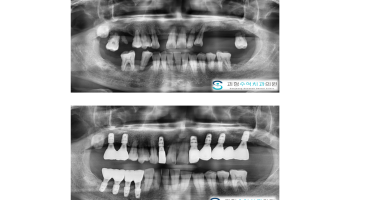

임플란트

다수의 치아를 발치해야하는 상태로 사용할 수 없게된 치아를 발치하고 임플란트를 식립하여 회복한 사례입니다.